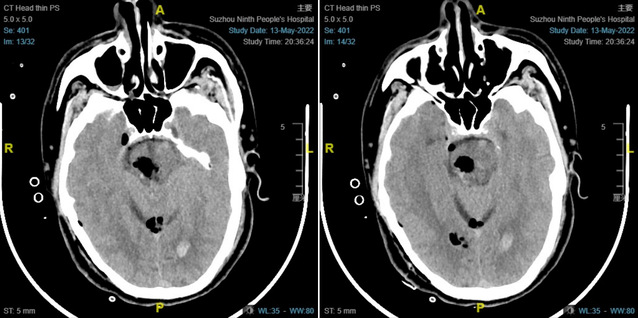

5月13日,患者蒋某某因突发昏迷由120急送至九院急诊抢救,急诊科医生接诊后迅速判断病情:患者昏迷,左侧肢体肌张力高,考虑脑出血可能。急查CT明确:脑干出血。患者脑干出血量大,严重危及生命。神经外科医师接到急会诊通知后迅速到场,并将患者收入神经重症监护病房行进一步诊治。

历经5个小时,手术取得了成功,术后复查CT示脑干血肿清除完全,减压充分。术后,神经重症医护团队为患者制定了详尽的治疗及护理方案。在医护的共同努力下,患者术后第二天意识即逐渐开始好转,术后第三天,可言语,肢体可活动。经过10余天的治疗,患者病情进一步好转出院。接下去,将进行下一步综合康复治疗。